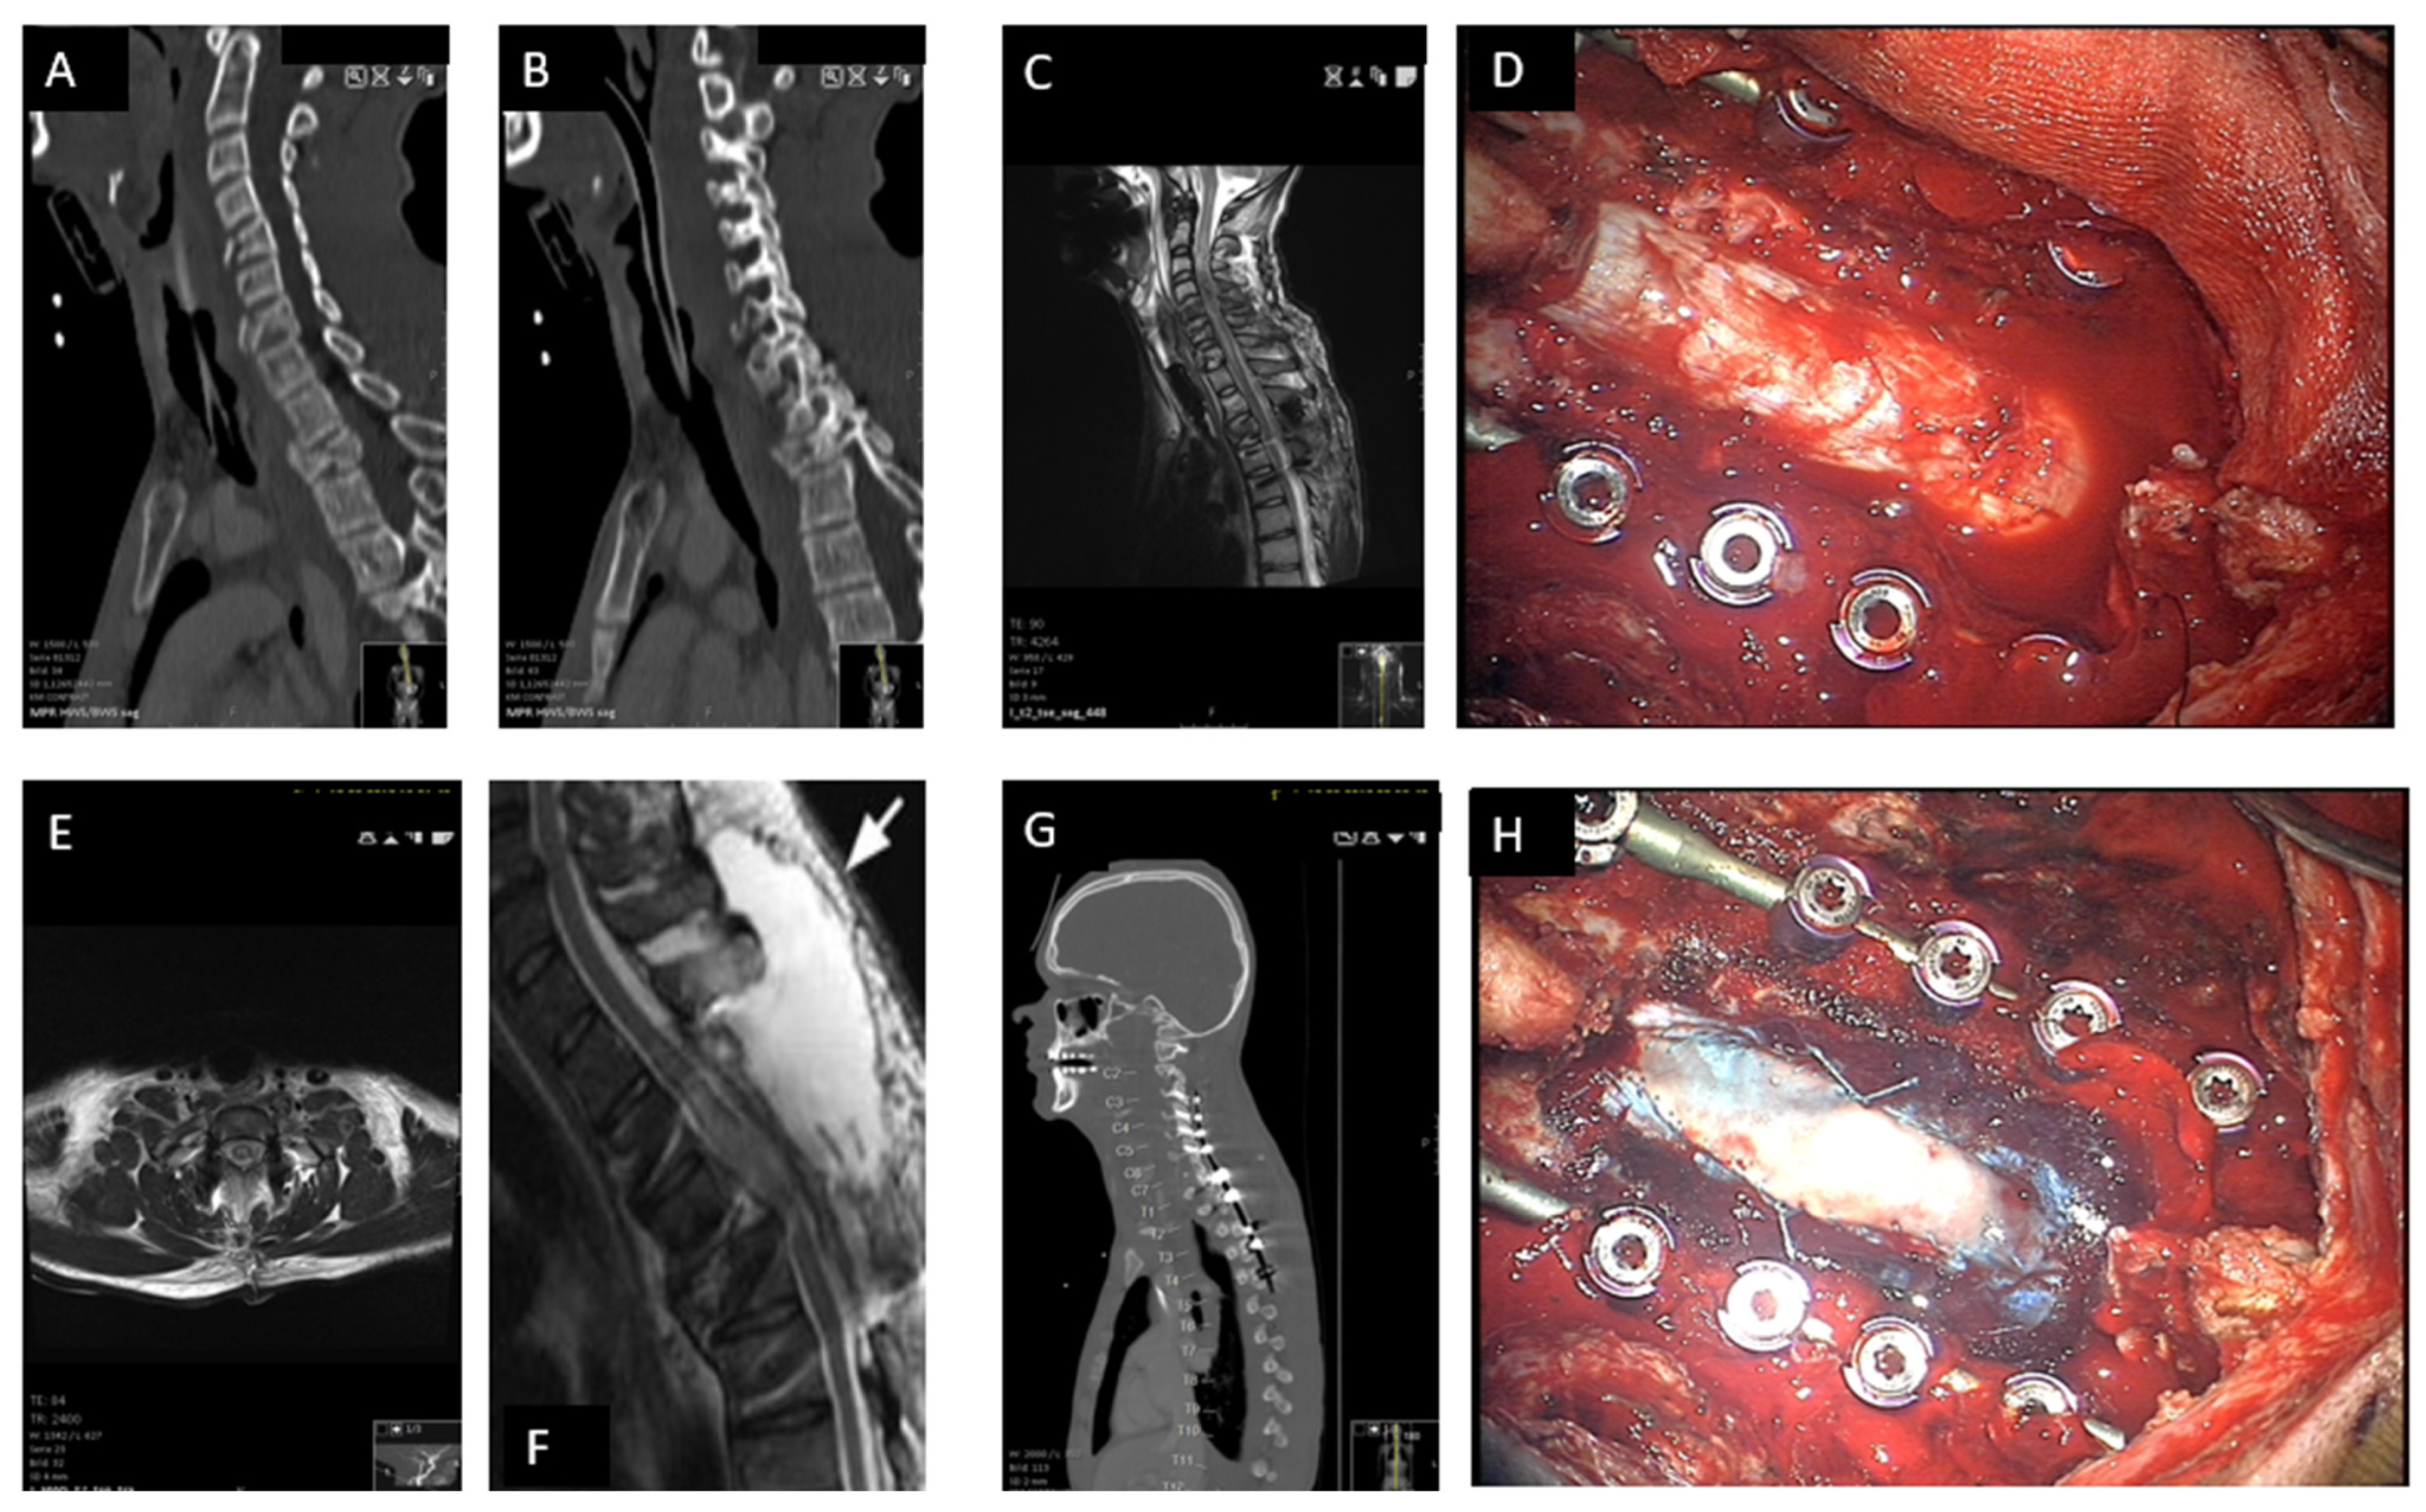

3.3. Surgical Technique of Decompressive Laminectomy and Expansive Duraplasty (Figure 2)